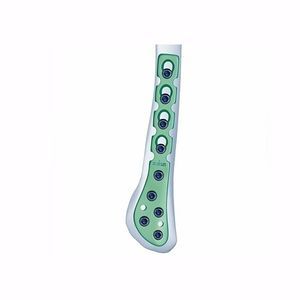

... 厚度: 2.3 毫米 宽度: 9.3 毫米 孔距13 毫米 材料: Ti-6Al-4V钛-6Al-4V 螺钉 - 3.5 毫米锁定螺钉/涡旋螺钉 - 2.4/2.7 毫米锁定螺钉 仪器 - 小型锁定器械套装 - 2.4/2.7 锁定板仪器套装 系列:小型锁定板 部件:远端 骨: 腓骨 描述 腓骨后外侧锁定接骨板,左侧,3 孔,77 毫米长 腓骨后外侧锁定板,左侧,4 孔,90 毫米长 腓骨后外侧锁定板,左侧,5 孔,103 毫米长 腓骨后外侧锁定板,左侧,6 ...

... 这种钢板和螺钉系统与PIONEER小型器械系统一起使用 ...

... 这种钢板和螺钉系统与PIONEER小型器械系统一起使用 ...

... 这种钢板和螺钉系统与PIONEER小型器械系统一起使用 ...